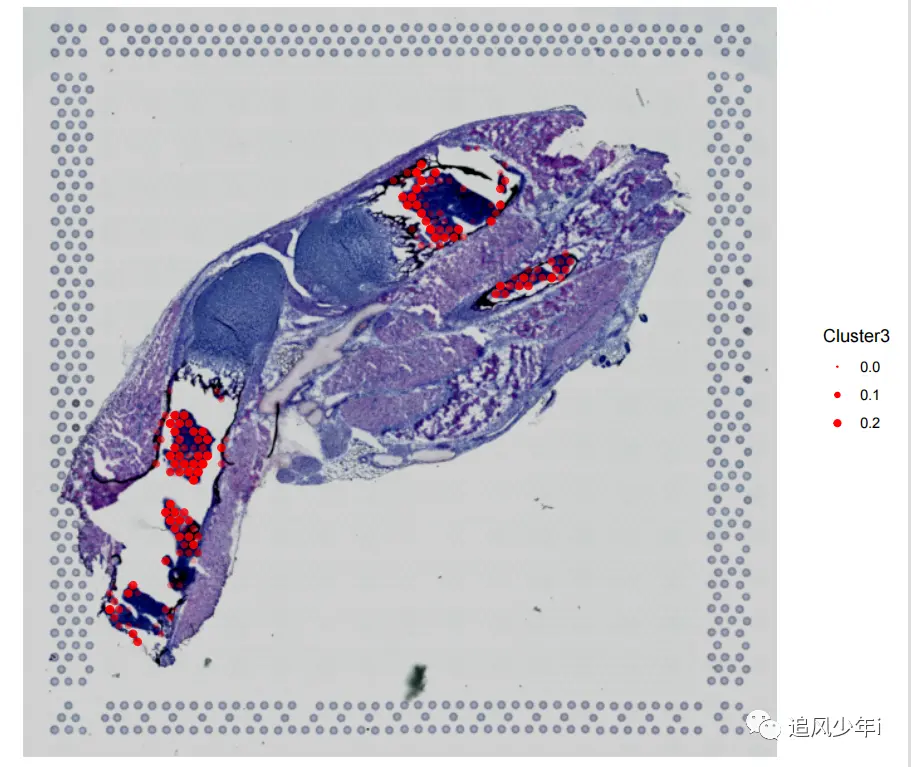

相信大多数还是利用Seurat来进行联合分析,如果用了其他软件,可以将联合的矩阵结果进行替换,我们还是以之前的结果为例,HE染色和单细胞空间联合分析的结果部分展示如下

画出来的效果如下图,颜色根据自己的喜好进行搭配

图例和配色有点差,我们来调整一下,首先调节一下图例的大小

好多了,借鉴一下第一张图的搭配

嗯,还行